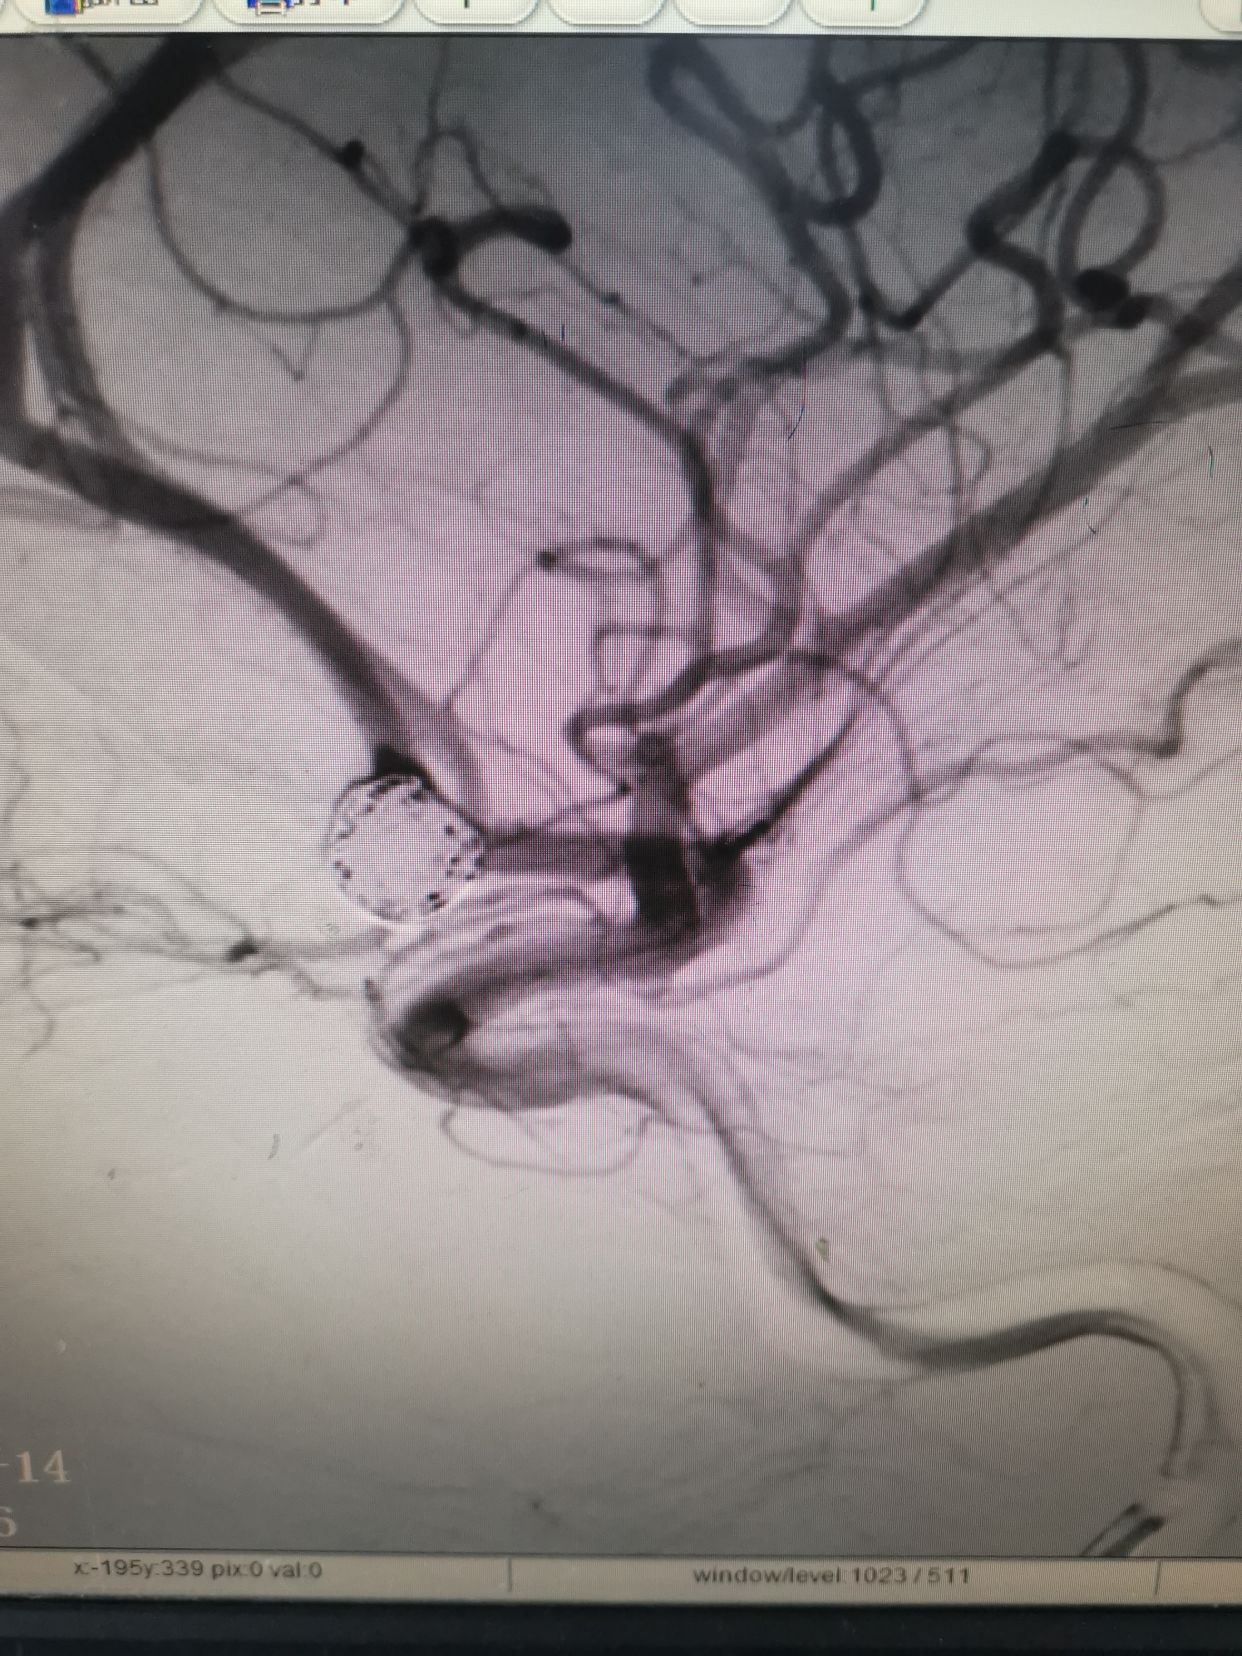

右侧颈内动脉造影。

左侧颈内动脉造影,发现一宽颈前交通动脉瘤。

造影过程中,患者出现意识障碍加深,烦躁,不能配合,考虑颅内出的增加可能。术中请麻醉科老师急诊行气管插管麻醉。后行左侧颈内动脉3D造影。